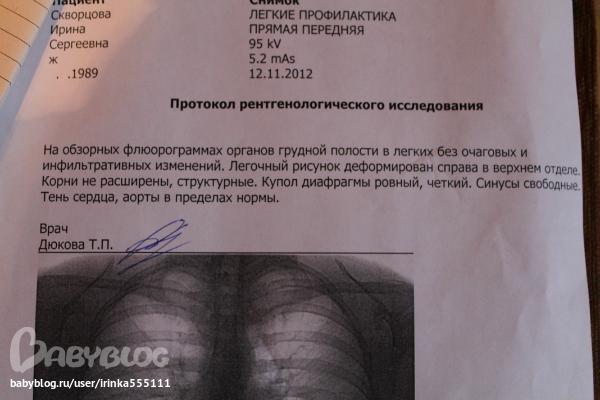

Фотографии рентгеновских снимков без необходимости направления от врача